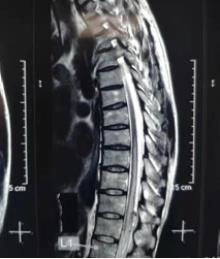

术前MRI可见胸8至腰1脊髓水肿,异常血管影像